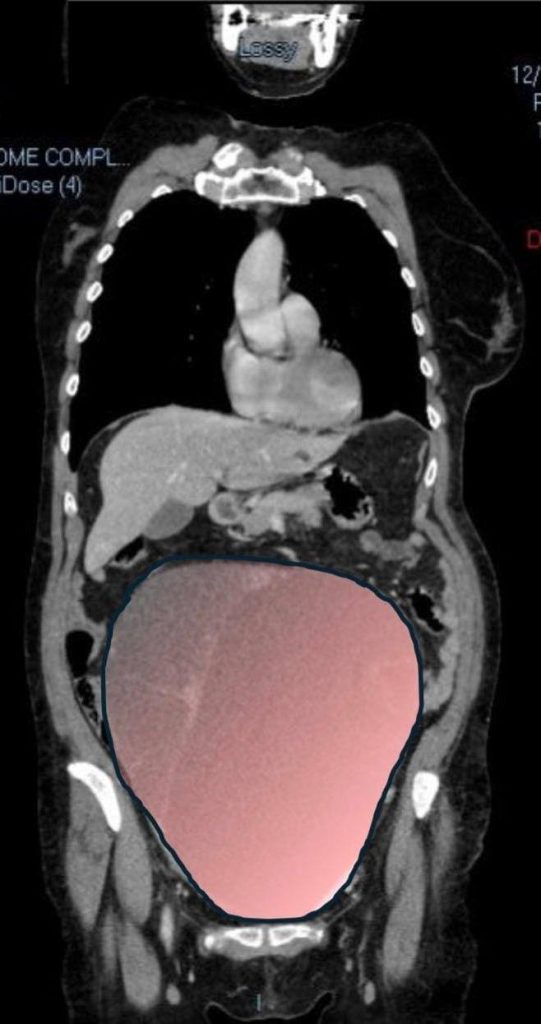

In a complex operation lasting around six hours, surgeons successfully removed the 28cm (1 in) tumour, which weighed a staggering 6kg (13lb).

The growth was described by the City of Health and Science of Turin as “comparable in volume to a full-term twin pregnancy”.